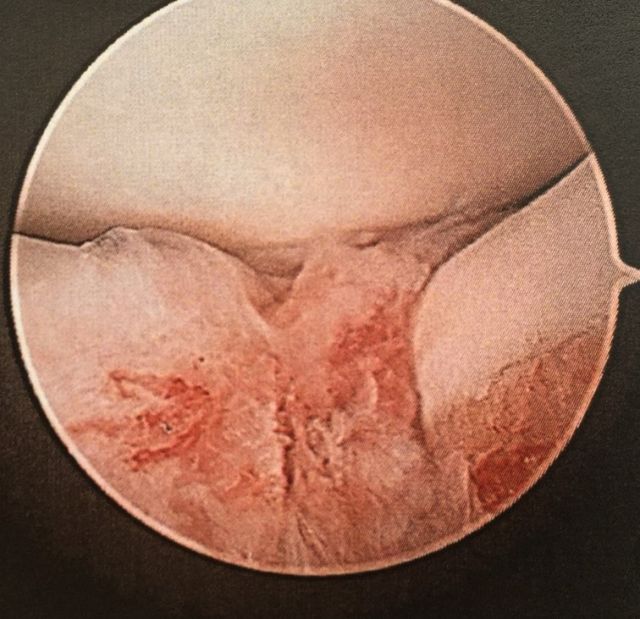

Arthroskopische Behandlung der Sesambeinchen und Beugesehne des Großzehens